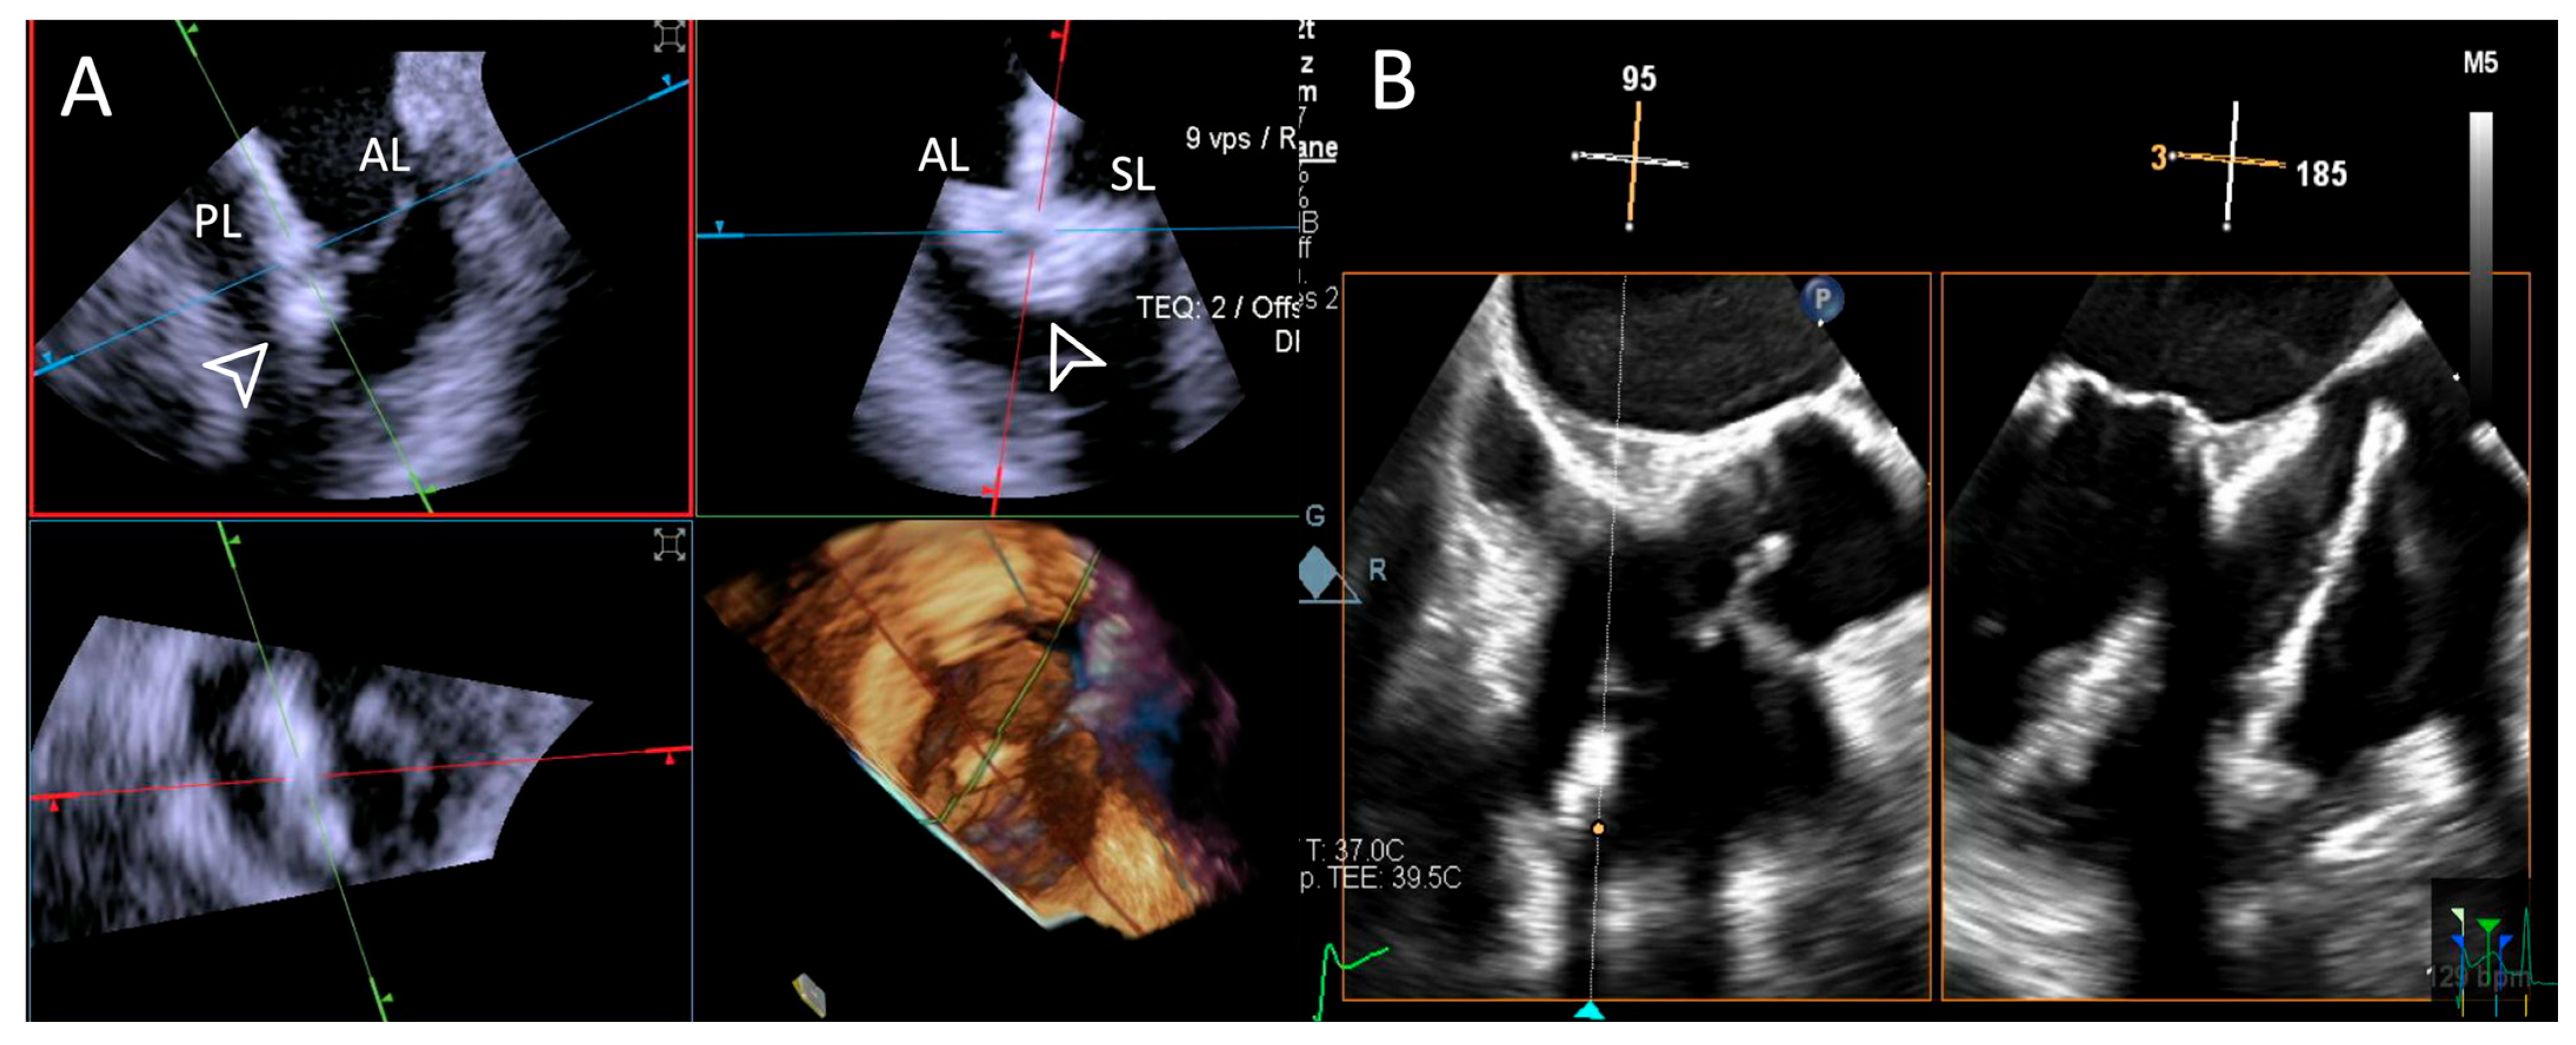

- Step number 7: leaflet insertion.

- Step number 8: evaluation of residual regurgitant jets.